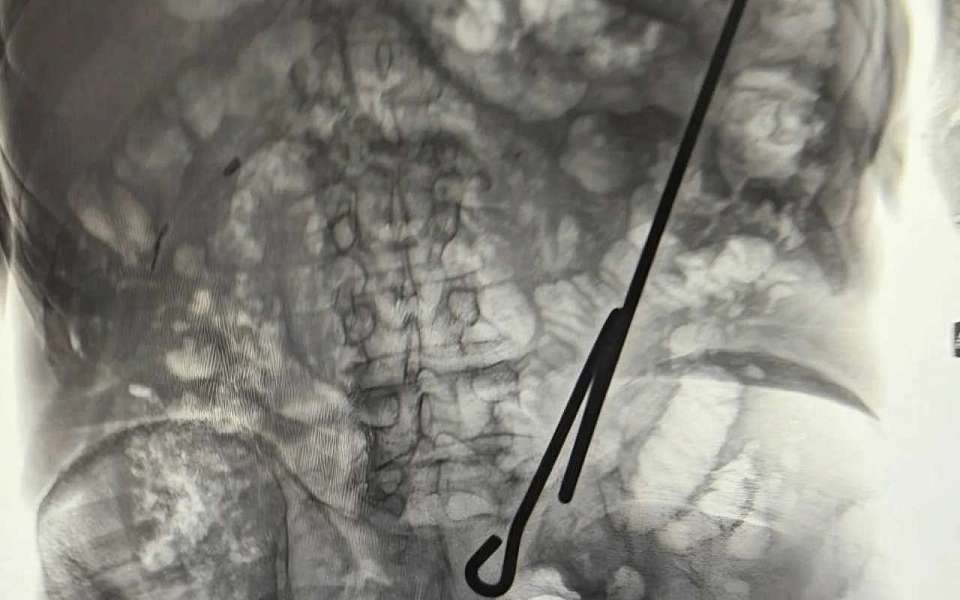

Сначала в отделение поступил пожилой мужчина 84 лет, получивший травму дома при падении на сделанный самостоятельно инструмент — железный крючок. Его сразу госпитализировали, провели обследование и экстренно прооперировали. Благодаря своевременному вмешательству врачам удалось аккуратно удалить крюк, избежав повреждений внутренних органов. Поскольку пострадавший был на тот момент голоден, операция прошла успешно, восстановительный период завершился благополучно, и вскоре пациента отпустили домой.